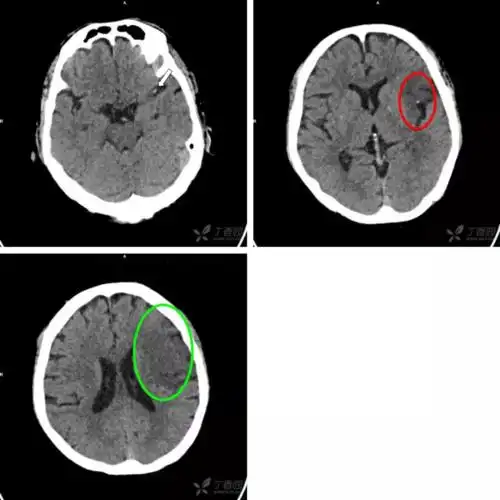

术后第二天复查ct,见血肿清除理想,但右侧大脑半球出现大面积脑梗塞

ct显示右侧豆状核轮廓模糊,接诊医生根据临床表现,怀疑急性脑梗塞.